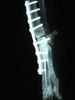

Die Arthrodese ist also eine operative Gelenkversteifung bei der die Bewegungsfähigkeit im Gelenk komplett unterbunden wird. Bei der Arthrodese wird der Knorpel der beiden Gelenksköpfe entfernt und eine Platte mit Schrauben zum Fixieren darübergelegt, so dass die beiden Knochen dort zusammenwachsen, wo vorher das Gelenk war. In den Spalt hat man bei der OP Knochensubstanz transplantiert. Fachlich genauer vermag ich das als Laie nicht zu erklären.

Das sind die schlimmsten Gedanken.... Obwohl sie nun unsinnig sind, das Gelenk ist ja nun versteift, sie hat eine Platte und 9 Schrauben durch die Knochen. Rückgängig kann man das ja nicht mehr machen. Manchmal wünschte ich, ich könne solche Gedanken einfach ausknipsen. Sie machen mich noch immer weinerlich und das kann ich gar nicht leiden. Hab ja nun wirklich genügend geheult in den letzten zwei Tagen.

Auf den ersten Blick sieht man auf den Bildern gar nichts, außer eben einem für den Laien erkennbaren Gelenk. Irgendwie dachte ich, da wäre nun keins mehr. Man kann die Platte gut erkennen, aber unmöglich sagen, wo da jetzt was wie und wie gut zusammengewachsen ist. Für mich sieht es aus wie ein Gelenk mit Platte drüber, alles etwas windschief. Ziemlich unbefriedigend, aber ich bin ja auch keine Fachfrau. Außerdem: Was erwarte ich denn?

Die Röntgenaufnahmen ergaben, dass die Platte super sitzt, keine Athrosen erkennbar sind, der Knochen schon recht gut durchbaut ist, keine Schraube sich lösen will. Insofern macht sich schon mal etwas Erleichterung in mir breit.